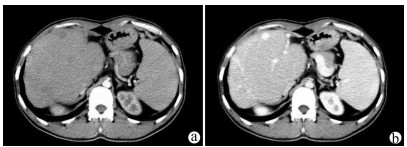

2021, 37(9): 2130-2135. DOI: 10.3969/j.issn.1001-5256.2021.09.025

摘要:

目的  探讨肝脏三维可视化重建技术在儿童复杂肝母细胞瘤肝切除术中的应用价值。  方法  回顾分析2018年1月—2020年10月于火箭军特色医学中心实施了以根治性切除为目的的肝肿瘤切除术的30例肝母细胞瘤患儿的临床资料,根据术前是否行肝脏三维重建(IQQA-Liver系统)将所有患儿分为三维重建组(n=15)和对照组(n=15),比较2组患儿围手术期临床参数以及短期预后和随访情况。符合正态分布的计量资料2组间比较采用独立样本t检验,不符合正态分布的计量资料2组间比较采用Mann-whitney U检验。计数资料2组间比较采用Fisher确切概率法。  结果  三维重建组较对照组平均年龄更大[(55.7±10.2)月vs (28.2± 2.7)月]、POSTTEXT Ⅲ/Ⅵ期(12例vs 5例)和肝静脉或下腔静脉受累者(11例vs 3例)更多,差异均有统计学意义(P值均<0.05)。所有患儿均顺利完成手术,2组在出血量、手术时间、肝门阻断次数/时间、行肝段及部分肝切除例数方面,差异均无统计学意义(P值均>0.05)。术后中位随访时间9.5个月,三维重建组2例复发,分别于术后10个月和12个月确诊,目前继续化疗中;对照组4例复发,高于三维重建组(P=0.651),其中2例在术后7个月复发接受肝移植存活至今,另有2例复发后短期内死亡。  结论  三维可视化重建技术有助于更安全精准实施复杂儿童肝母细胞瘤肝切除术,尤其是可以使部分POSTTEXT Ⅲ/Ⅵ期患者安全实施扩大肝切除,从而避免行肝移植。